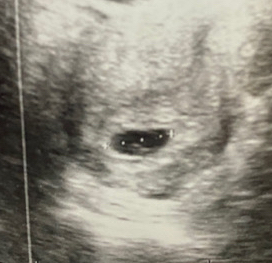

سونار بطن = تعكسين

سونار مهبل =ماتعكسين

من الاسبوع 6 الى الاسبوع 8 فقطططط

لا اقل ولا اكثر

فيه بقعه مضيئه في كل سونار ركزي فيها